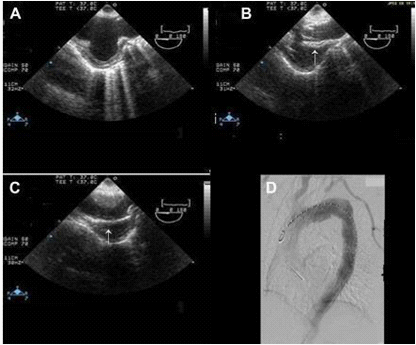

In contrast, Echo Doppler has been recognized as a good option to these techniques due to its low cost, easy implementation and interpretation and the absence of exposure to any type of radiation.26 This provides a better understanding of the endoleak formation mechanism and provides a more accurate analysis thereof, due to a collateral circulation. The origins of an endoleak may also be correctly identified. Compounded by the fact that it allows visualize blood flow in the aneurysm sac and its direction. This seems to be an excellent tool in the evaluation of high flow endoleaks within the aneurysmal sac. It is an imaging technique commonly used in vascular studies, being easy to perform, inexpensive, portable, secure and highly available. Its use for patients’ follow-up can reduce the biological hazards associated with CT angiography, since this frees the body of the individual to a substantial dose of ionizing radiation. The advantage of Doppler ultrasound in patients’ follow-up with aortic stent graft is that it allows a serial measurement over time of the residual diameter of the aorticaneurysm sac. Doppler ultrasound is more accurate than CT for the detection of problems associated with stent graft patency, their migration, kinking and stenosis. Provides physiological and anatomical information at the same time, unlike CT. The ability to quantify and compare serial images at a low cost without contrast and radiation, suggests that this technique should be the Gold Standard in the follow-up to TEVAR (Figures 5-9).20,24,27

Figure 5 Image showing (A) arch aneurysm, (B) partially deployed stent graft (arrow), and (C) fully deployed stent graft (arrow). (D) Post procedure angiography showing stent grafts in place.28